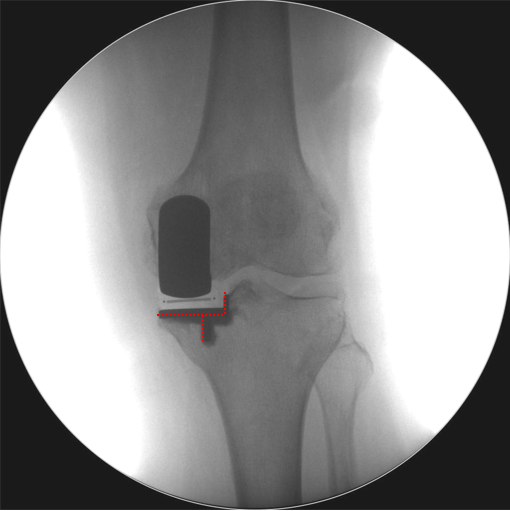

辨认bearing内的标识(透视片正位)

bearing 内的标识:点和线段“ .—. ”线段显示为“—”在前;点显示为“.”在后

Bearing 中立位( X-ray正位)

Bearing 内旋( X-ray正位)

Bearing 外旋( X-ray正位)